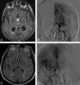

The leptomeningeal collateral circulation (also known as leptomeningeal anastomoses or pial collaterals) is a network of small blood vessels in the brain that connects branches of the middle, anterior and posterior cerebral arteries (MCA, ACA, and PCA), with variation in its precise anatomy between individuals. During a stroke, leptomeningeal collateral vessels allow limited blood flow when other, larger blood vessels provide inadequate blood supply to a part of the brain. [Source: Wikipedia ]